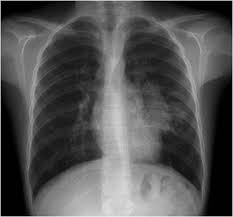

- PA akciğer grafisi

- Mediasten genişleme

- Timik hiperplazi, genellikle düzgün kenarlı, diffüz ve simetrik genişlemiş timus dokusu olarak görülür. Asimetrik genişleme timoma olasılığını artırır (Resim 1